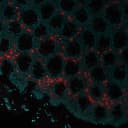

Peripheral blood granulocytes are classified into neutrophils, basophils and eosinophils according to the staining characteristics of their cytoplasmic granules. Granule proteins are released by physiologic and pharmacologic stimuli and play important roles in both normal and pathological host immune responses. Eosinophil major basic protein and eosinophil peroxidase (EPX) are granule proteins specific to the eosinophil. AHE-1 recognizes human EPX, a granule protein specific to eosinophils. It does not cross-react with eosinophil major basic protein, elastase, cathepsin G, esterase N, thrombin, plasmin, kallikrein, lactoferrin, or transferrin. This MAb stains eosinophils only and does not stain other peripheral blood cells, including platelets, neutrophils, monocytes, lymphocytes or red blood cells. Human EPX gene product can form a tetramer of two light chains and two heavy chains. Other peroxidase family members include myeloperoxidase (MPO), lactoperoxidase (LPO), and thyroid peroxidase (TPO)._x000D_ _x000D_ Primary antibodies are available purified, or with a selection of fluorescent CF® Dyes and other labels. CF® Dyes offer exceptional brightness and photostability. Note: Conjugates of blue fluorescent dyes like CF®405S and CF®405M are not recommended for detecting low abundance targets, because blue dyes have lower fluorescence and can give higher non-specific background than other dye colors._x000D_ _x000D_Synonyms:

IF (verified)Validated Applications:

IFField of Research:

ImmunologyPositive Control:

MCF-7 cells. TonsilConcentration: